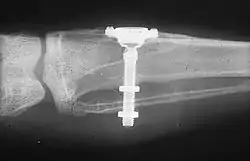

The design of implants has to account for a lifetime of real-world use in a person's mouth. Regulators and the dental implant industry have created a series of tests to determine the long-term mechanical reliability of implants in a person's mouth where the implant is struck repeatedly with increasing forces (similar in magnitude to biting) until it fails.[30]

Primary implant stability refers to the stability of a dental implant immediately after implantation. The stability of the titanium screw implant in the patient's bone tissue post surgery may be non-invasively assessed using resonance frequency analysis. Sufficient initial stability may allow immediate loading with prosthetic reconstruction, though early loading poses a higher risk of implant failure than conventional loading.[63]